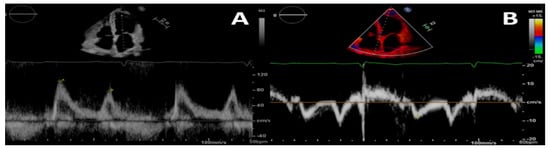

Figure 1.

Pulsed-wave Doppler (A) and tissue-Doppler (B) imaging of the left ventricular basal septum for a 4-chamber apical view in a patient with CKD. This shows a second-degree diastolic dysfunction pattern in A; the E/e’ ratio indicates a likely rise in left ventricular filling pressures.